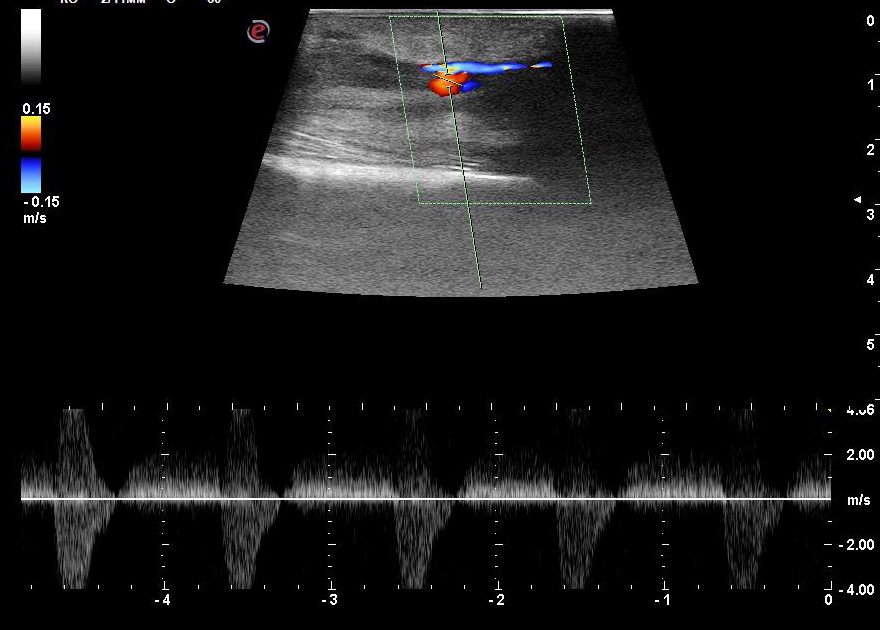

Repeat duplex scanning of the upper limb arteries: the aneurysm cavity spread to the upper third of the upper arm (Figures 3, 4), with the main type blood flow through the RA. Under ultrasound guidance, compression was applied in the area of the pseudo-aneurysm neck.

Fig. 4. Repeat Duplex scan (the second day), spectral Doppler mode, longitudinal section. The blood flow in the neck of the radial artery pseudoaneurysm is shown.